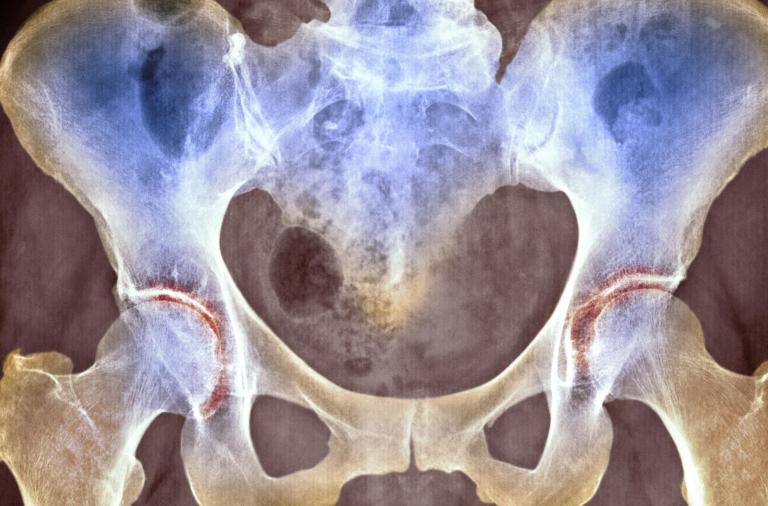

1、髋骨关节炎引发的疼痛

如果在关节的软骨出现变形性病变的时候,也会引发疼痛,这种疼痛最开始是没有明显的症状,只有在活动之后才会出现疼痛感。 这软骨关节出现变形之后,疼痛感不是持续存在的,而是在休息之后有所减轻,但是在受凉或者受潮湿的情况下也会加重疼痛感。

如果是在髋关节前方或者是侧面出现疼痛问题的话,就有可能是关节软组织变形引发的问题。 最关节软组织变形之后,除了会引起疼痛感之外,还有可能在早上醒来的时候感觉局部僵硬,必须在活动之后才能得到缓解。 如果情况比较严重的话,还有可能导致这一关节出现功能性障碍。